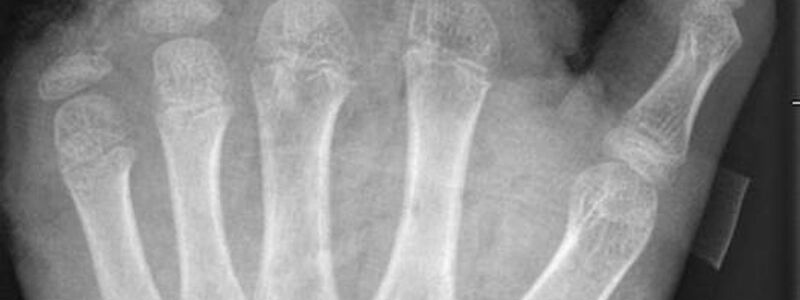

Abgetrennte Finger, durchtrennte Sehnen, Amputationen - die Handchirurgin Leila Harhaus-Wähner hat in der Silvesternacht schon vieles gesehen. Auch in diesem Jahr rechnet die Berliner Ärztin mit zahlreichen Böller-Verletzten. «Für Handchirurgen ist es klar, dass Silvester die arbeitsreichste Nacht sein kann.» Bis 24 Uhr passiere erstmal nicht so viel, ab 1 Uhr, 2 Uhr nachts kämen immer mehr Verletzte in die Notaufnahme und dann «sehr viele in sehr kurzer Zeit.»

In der Handchirurgie müssten an Silvester im Unfallkrankenhaus rund 20 bis 40 Menschen mit Böllerverletzungen operiert werden, sagt die Ärztin. Dieses Jahr werde sie mir vier weiteren Handchirurgen im Einsatz sein. Die häufigsten Verletzungen entstünden durch explodierende Böller in der Hand.

«Der überwiegende Teil der Verletzungen trägt tatsächlich lebenslange Folgen mit sich, weil die Sprengkraft dazu führt, dass eben nicht nur einzelne Strukturen verletzt sind, sondern immer mehrere. Und das heilt praktisch nie ganz folgenlos ab.» Zum Teil könnten Hände nicht mehr gerettet und müssten amputiert werden.